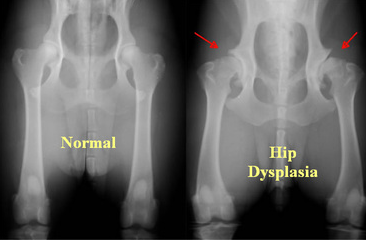

5. Babas wat gebore word met ‘n heupgewrig wat maklik uit die potjie kan glip, word in ‘n ‘padda’-spalkie geplaas sodat die heuppotjie reg kan ontwikkel om die kop van die bobeen in die potjie te anker.

6. Lees meer oor heup ontwrigting: https://www.mayoclinic.org/diseases-conditions/hip-dysplasia/symptoms-causes/syc-20350209